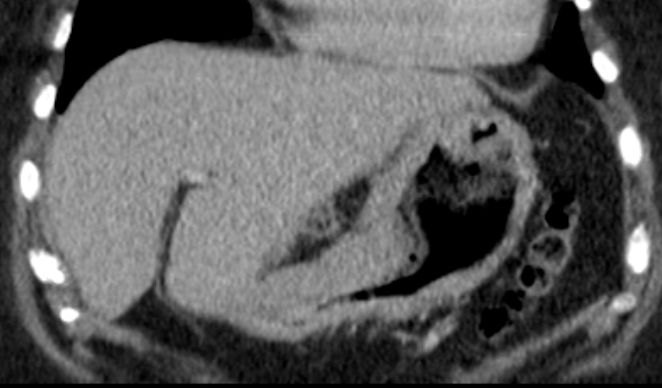

| Magenantrum | 54-jährige Frau mit obstruierendem Magenantrumkarzinom. ![]() |